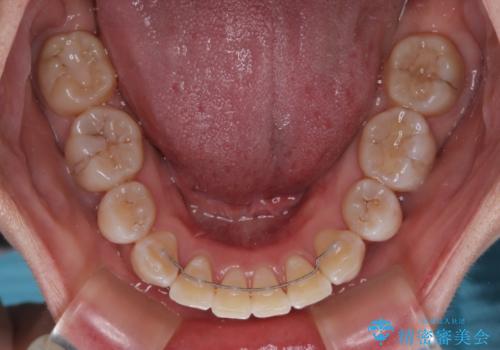

- メタルブラケット

- 2年6ヶ月

ご本人がびっくりするくらい劇的に口元の突出感が改善され、大変満足のいく仕上がりとなりました。

- 矯正治療後の保定が不十分だと後戻り(元の位置に戻ろうとする動き)をします